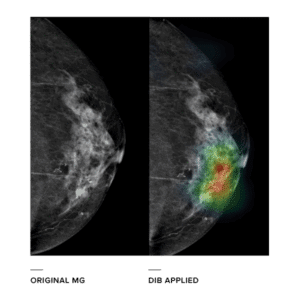

In contrast to conventional Computer-Aided Detection (CAD) that is heavily dependent on guidance (lesion annotation) of radiologists, DIB lets the machine define important diagnostic features by itself solely from large-scale data. This can be possible by employing feature-learning capability of deep convolutional neural network.

DIB for Mammography is designed to improve breast cancer detection rates in mammography, mainly focused on breast cancer detection in dense breast, an aspect of breast cancer screening widely regarded to be most challenging. Although it is in the early stages of development, Lunit’s DIB for mammography aims to 1) detect and localize lesions, 2) suggest their BI-RADS categories, and 3) predict their malignancy probabilities.